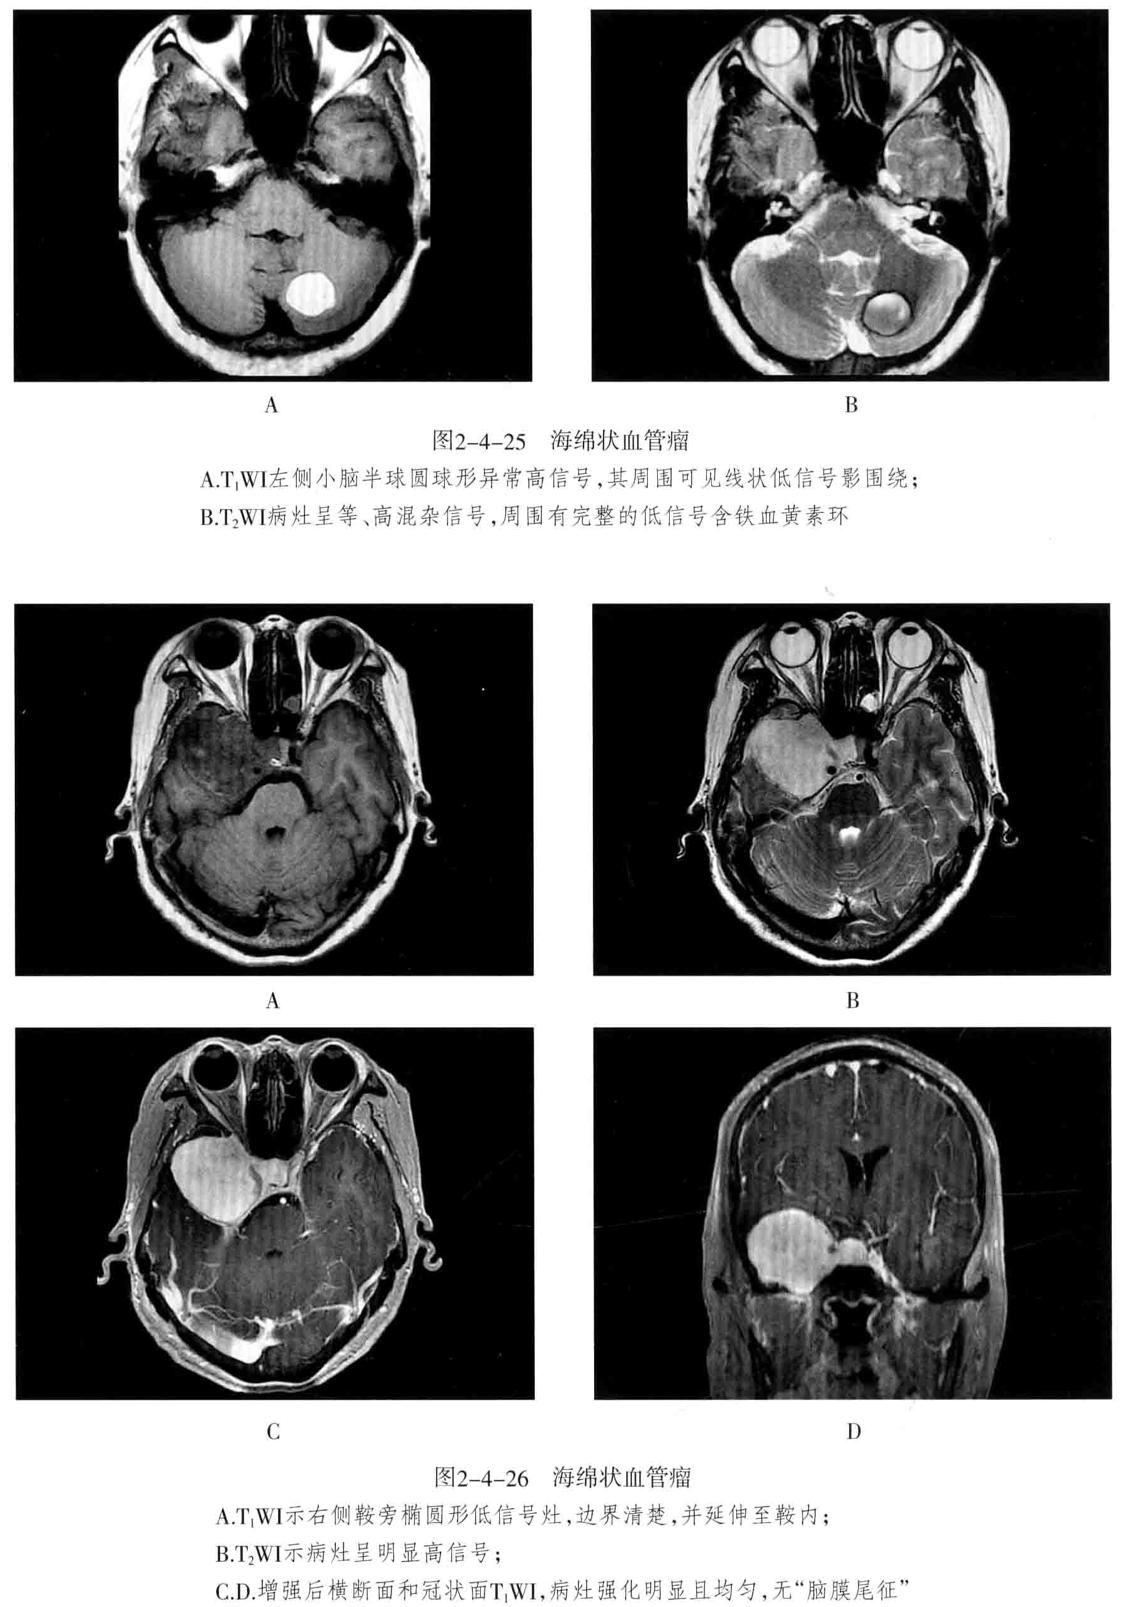

- 鉴别诊断: 海绵状血管瘤在T1WI、T2WI上均混杂信号,境界清楚病灶内无流空效应,T2WI病灶周围可见低信号含铁血黄素环,使病灶呈“爆米花”状,具有特征性,增强扫描病灶轻度-明显强化(与病灶内血栓及钙化量多少有关,血栓少则强化明细)。

- 海绵状血管瘤 : 病变主要由不规则、大小不等的薄壁海绵状血窦组成,其间有增生的胶质组织,没有正常的神经组织,可反复少量出血,常有不同程度的钙化和含铁血黄素沉着。可发生于脑内(常见于大脑半球各叶)、脑外(常见于颅底)。常无任何症状,或表现为癫痫等。

- MRI检查:T1WI多呈高信号、稍高信号或混杂信号,T2WI上呈高、低混杂信号,典型者呈“爆米花”状,境界清楚,病灶周围有含铁血黄素沉积,T2WI是表现为低信号环。病灶内及周边无流空血管影。病灶无占位效应,周围脑组织无水肿。大量出血时,表现为病灶短期明显增大,可有占位效应。增强后脑内者病灶可轻度强化,亦可无强化。脑外者多于颅底鞍旁,T1WI低信号,T2WI明显高信号,边界清楚,增强后明显强化且强化均匀。